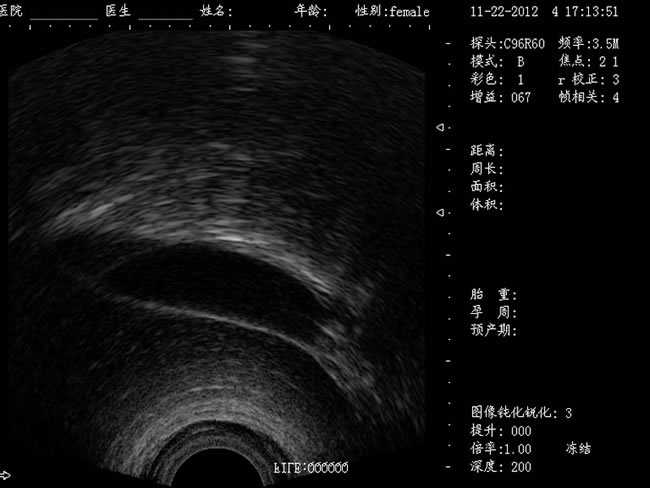

DW-460

功能特點:

婦產科手術監視儀-可視人流機掃描角度:

a) 6.5MHz腔內探頭:152º可視可調;

b) 3.5MHz凸陣探頭:60º可視可調;

TGC 調節:總增益、8 段TGC 調節器。

圖像放大:實時放大(16 級可調),局部放大(≥2 倍)。

圖像調節:黑白、左右、上下、亮度、對比度、焦點數、焦點間距、焦點位置、動態范圍、掃描角度、掃描線密度、聲功率、幀相關、M 速度。

圖像處理:圖像平滑/銳化、組織諧波、伽瑪校正、直方圖。

注釋功能:日期,時鐘,姓名,病歷號,性別,年齡,醫生、醫院、全屏幕字符編輯。

體位標記:≥30 種。